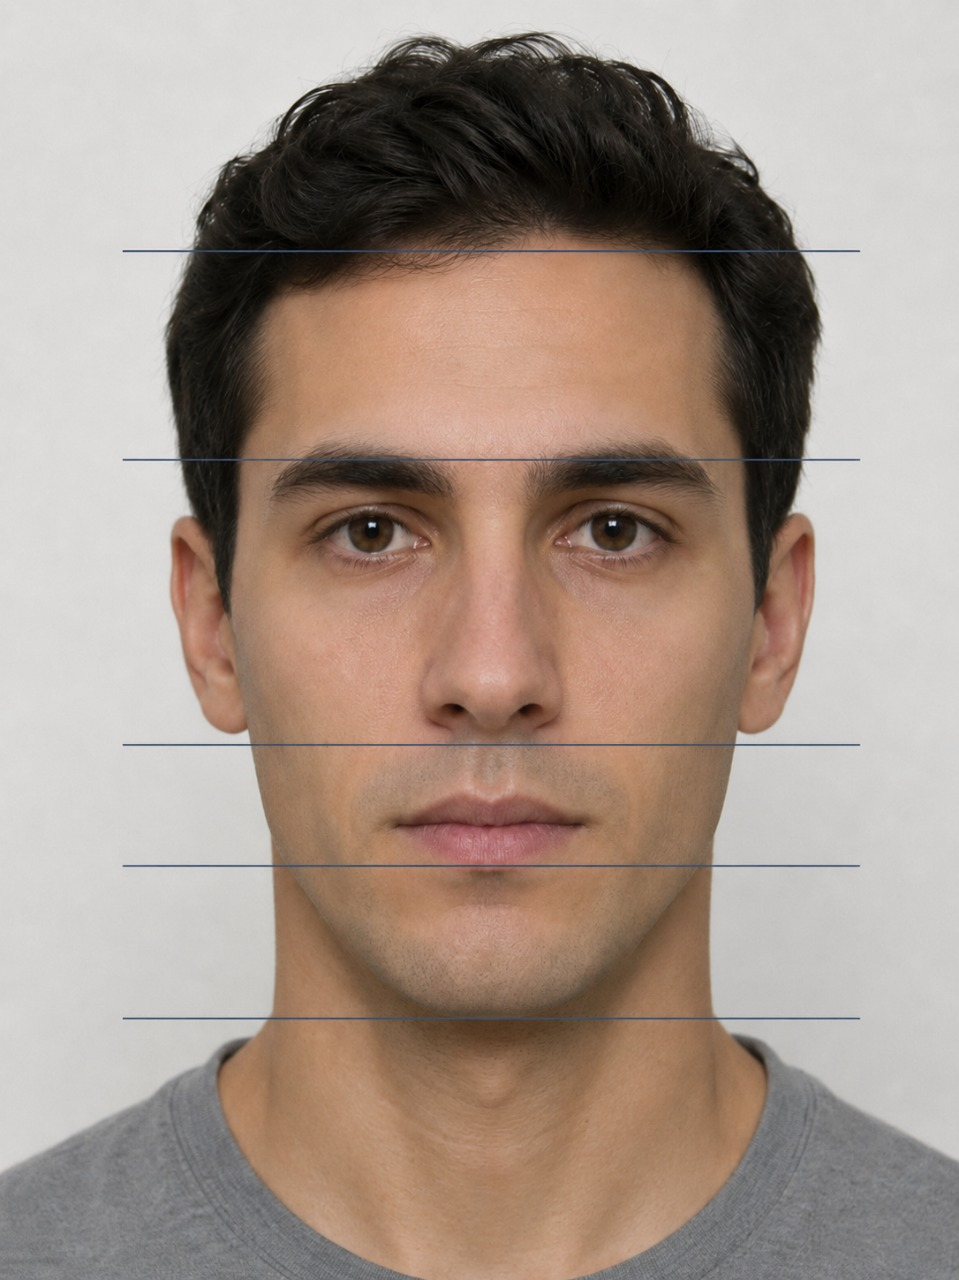

Привлекательная улыбка имеет свои вполне четкие стандарты:

- Линия верхних зубов (арка улыбки) должна быть параллельна нижней губе.

- Улыбка должна быть широкой. Чем больше зубов видно в момент улыбки, тем более привлекательной и открытой она воспринимается окружающими.

- Средняя линия улыбки должна совпадать с центром лица.

- Кроме того, чем заметнее при улыбке верхние зубы пациента, тем моложе он кажется. И, наоборот, демонстрация при улыбке нижних зубов добавляет годы.

Поэтому ортодонт обязательно учитывает все выше перечисленные параметры и планирует

такое передвижение зубов, чтобы, исходя из имеющихся возможностей, сделать улыбку

пациента максимально приближенной к идеалу. После грамотного ортодонтического лечения

пациент будет выглядеть более молодым и привлекательным без всякой пластической хирургии.

Результаты таких расчетов тоже отражаются в плане лечения.